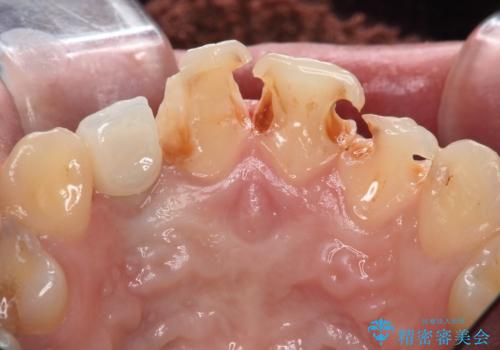

- 虫歯の治療を繰り返した前歯の見た目の改善を求めて来院されました。

大きく詰められたコンポジットレジンと虫歯の再発が見られ、経年劣化により審美性も損なわれていました。

充填されたコンポジットレジン・再発した虫歯を神経に影響が出ないよう丁寧に除去し再充填をしたのちオールセラミッククラウンで前歯の審美性を回復します。